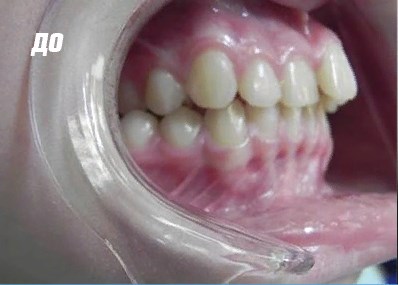

Результат лечения

Исправление прикуса с помощью пластинки на зубы ребенку

Съемная пластинка на зубы ребенку из пластика изготавливается в лаборатории на основе слепков обеих челюстей маленького пациента. Конструкция оснащена крючками и пружинками, их натяжение регулируется ортодонтом. Пластинки важно носить, круглые сутки, снимая их только для приема пищи.

Исправление прикуса с помощью специальной капы

Для изготовления капы слепки не нужны. Врач-ортодонт проводит замеры в полости рта ребенка специальной линейкой и подбирает капу подходящую по размеру и типу. Капы, в отличие от пластинок, не требуется носить постоянно. Достаточно надевать их на время ночного сна и днем на пару-тройку часов. Капы можно использовать для коррекции прикуса с самого раннего возраста.

Исправление прикуса с помощью брекет-системы

Эта конструкция является несъемной. В нее входит металлическая дуга, различные пружинки, лигатуры и собственно брекеты. Система давит определенным образом на зубы, вынуждая их принять правильное положение. Брекеты можно носить детям, у которых уже все молочные зубы заменились постоянными – обычно после 12 лет.